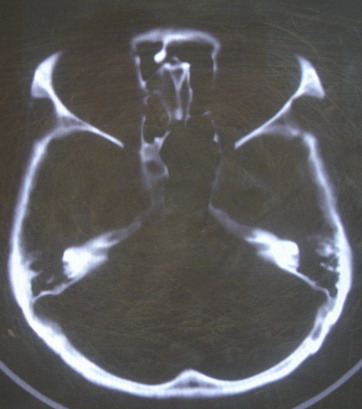

女 63岁 左额部碰伤

现有资料未见骨折表现

左枕部颅缝略增宽并轻度错位,建议结合临床,必要时复查

未见明显骨折

未见异常.

未经高分辩率处理。未见明显异常。

左额部未见明确骨折

左侧颞枕部颅缝分离骨折可疑。建议结合临床,必要时复查。

都错位了,当然是报骨折了。

左侧颞枕部颅缝分离骨折可疑。

结合临床,排除左侧颞枕部颅缝分离骨折可能。